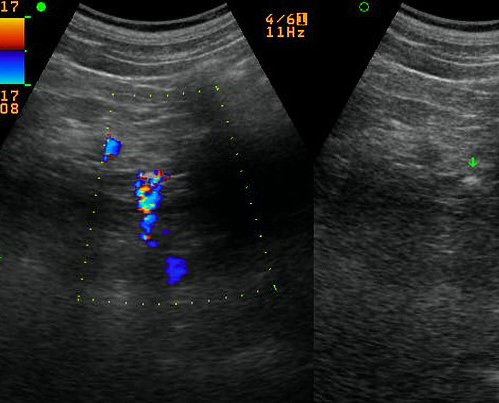

80% de calcul du canal

choledoque est faible de detecte par sa petite

taille et par le moindre de

zone hypoacoustique posterieure . Echo en Doppler

peut donner aspect de artefact scintillement a

posterieure du calcul " aliasing artefact " (

twinkle artefact ) et cette technique peut en

comsomation de augmenter de chance de detecte des

petits calculs obcurcir |